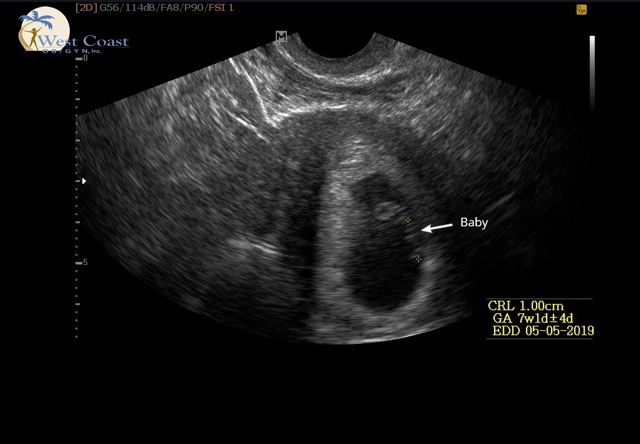

Ramzi theory anyone??

First US today. Thought we were 8w 1d but measuring at 7w 1d. Heart rate is strong. Any thoughts?!